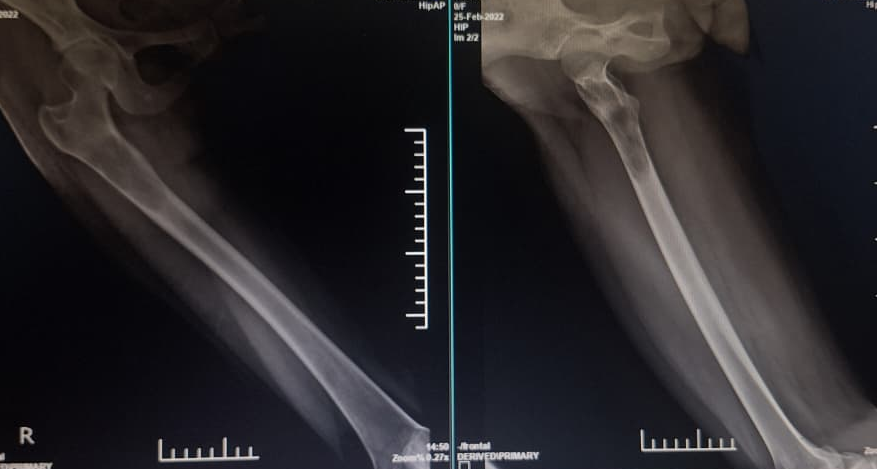

A young 23 year old female first presented in 2015 with complaints of right-sided chest pain and swelling. A thorough clinico-radiological evaluation was done and general surgeon consultation sought. Imaging revealed an expansile lytic lesion of the right 9th rib (Fig 1). Other long bone x-ray evaluation was done and found no abnormalities. We planned for excision biopsy of 9th rib and patient underwent surgical excision (Fig 2). Histopathological examination confirmed a benign intraosseous hemangioma(Fig 3). Post-operative recovery was uneventful. 6 monthly followed by yearly radiological follow-up was being done till pre-covid period. Patient lost to follow-up during 2020-2022 Covid-19 period.

In 2022, the patient presented with progressive pain and restricted range of motion of the right hip following minor trauma. She was re-evaluated clinically and imaging was done. Radiographs (Fig 4 ) and MRI (Fig 5) revealed an expansile lytic lesion of the right proximal femur consistent with intraosseous hemangioma. Due to risk of pathological fracture we planned for fixation of right proximal femur. She underwent right proximal femoral bone excision biopsy and dynamic hip screw fixation with iliac–fibular strut bone grafting (Fig 6). Post-operative period was uneventful. Started partial weight bearing after 45 days followed by full weight bearing by 90 days. Very good radiological incorporation of graft noted and fixation was stable radiologically (Fig 7). Histopathology report suggestive of benign bone hemangiomatous tissue without any features of malignancy (Fig 8).

• 2015: Expansile lytic lesion of right 9th rib with cortical thinning (Fig 1).

• 2022: Lytic right proximal femur lesion with risk of pathological fracture (Fig 4).